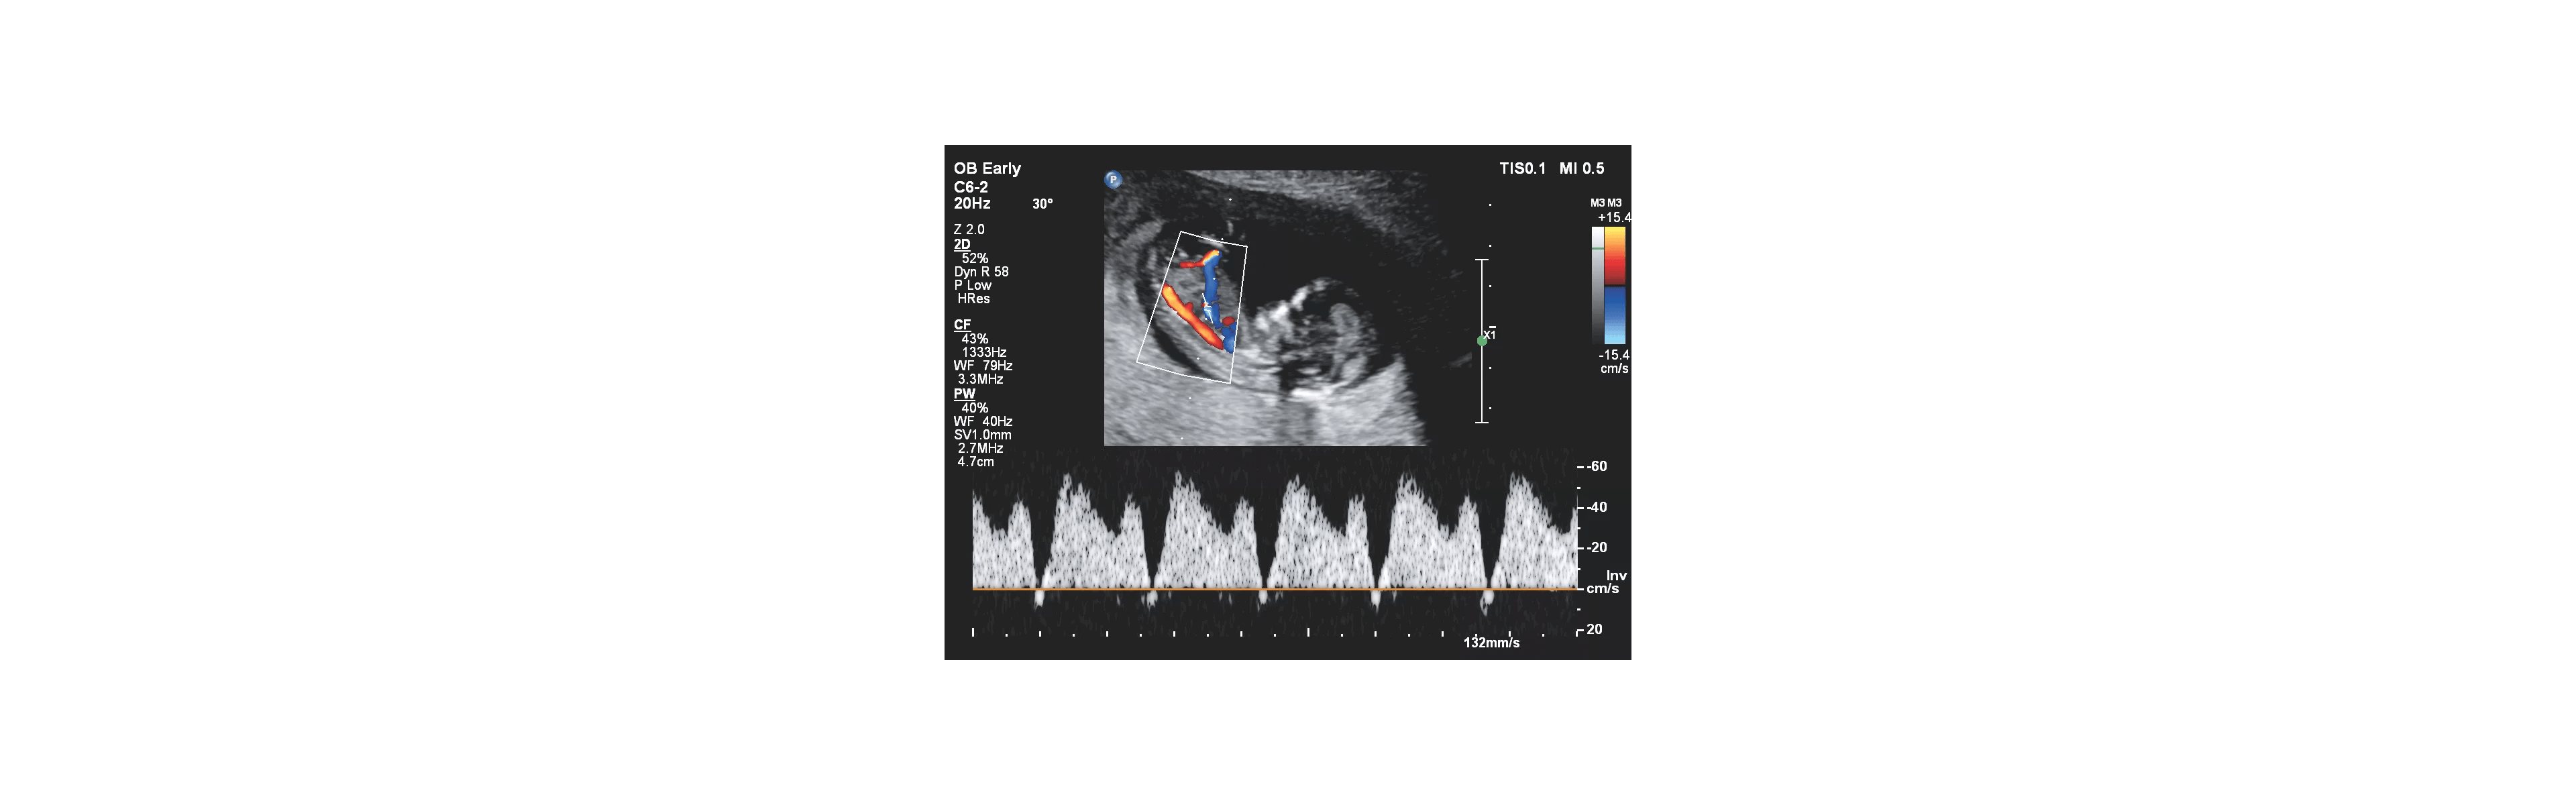

Vroegtijdige detectie van galstenen, nierstenen, cystes, myomen, of zwangerschap.

Beoordelen van buikklachten of pijn in de onderbuik zonder eerst naar een specialist te verwijzen.

• opsporen van vocht in de buik of longen

• beoordelen van spier- of peesproblemen